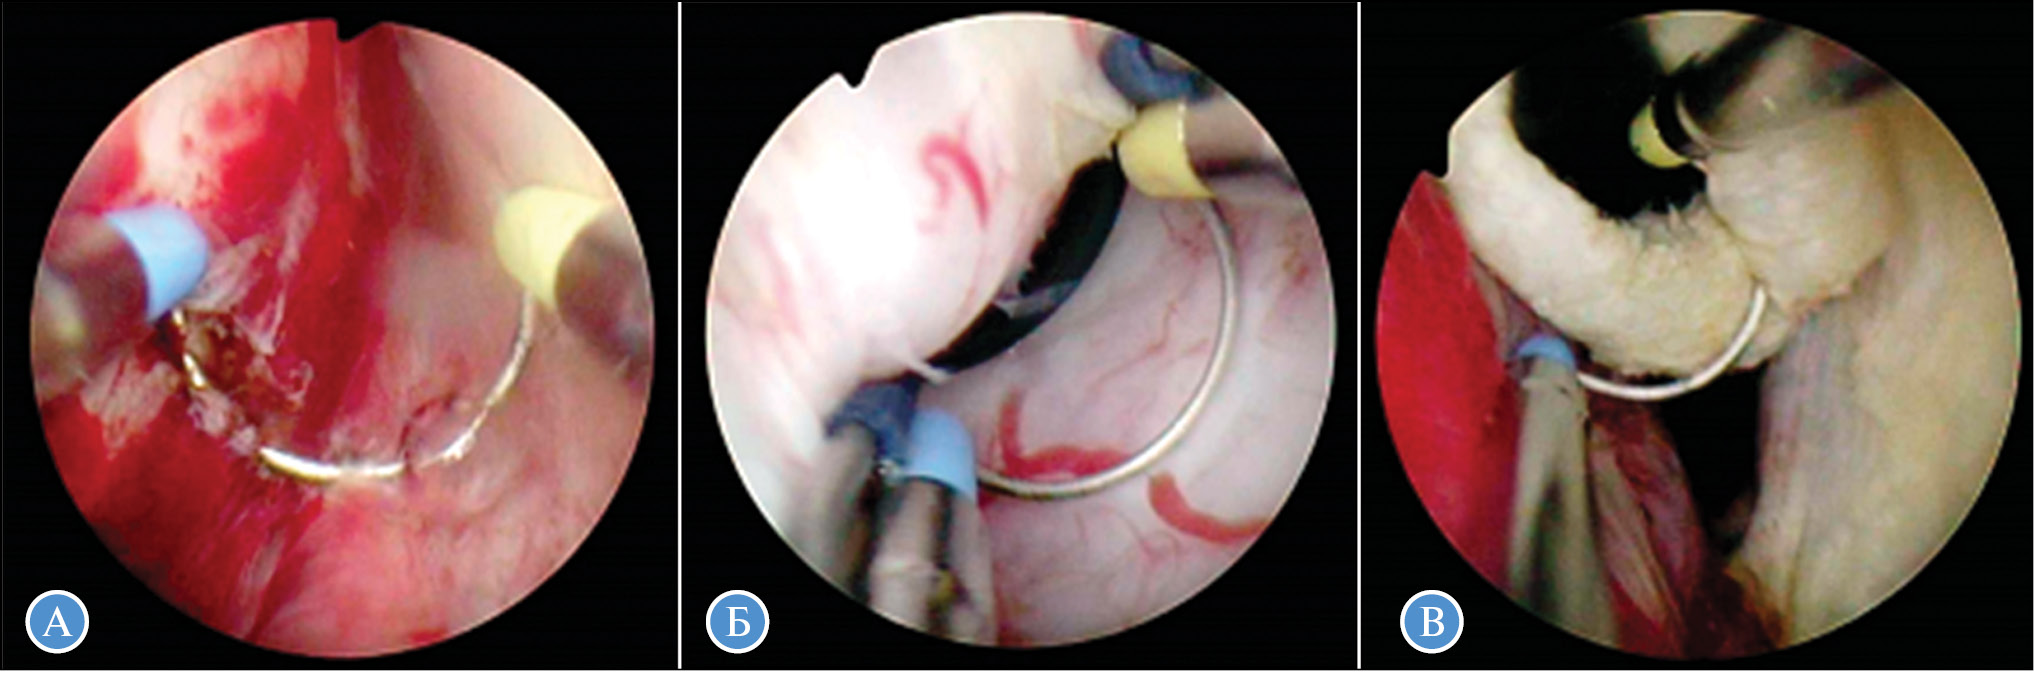

Модифицированный начальный этап плазменной трансуретральной энуклеации простаты разработан с целью снижения частоты случаев послеоперационного стрессового недержания мочи, которое в 3–5% случаев является следствием травматического повреждения наружного уретрального сфинктера. Модификация оперативной техники заключается в создании доступа к железе с применением новых анатомических ориентиров для максимального сохранения переднего фибростромального комплекса. Начальный разрез слизистой производится ВЧ-электродом Plasma-Needle и имеет Y-образную форму — от шейки МП до середины уретры по передней поверхности, следующие два разреза производят в правую и левую стороны до дистальной части простаты, что позволяет максимально сохранить область сфинктера в передней дистальной части. При стандартной операции эта зона обычно энуклеируется вместе с остальной простатой, с травмой части сфинктера уретры. Последующие этапы операции производятся по стандартной схеме плазменной трансуретральной энуклеации простаты (рис. 3).

Рис. 3. Модификация первого этапа плазменной трансуретральной энуклеации простаты при доброкачественной гиперплазии простаты больших и гигантских размеров с сохранением наружного сфинктера уретры: А — разрез от шейки МП в дистальном направлении по передней поверхности; Б — боковые разрезы на 13 и 23 часах УЦ; В — циркулярное рассечение слизистой вокруг семенного бугорка до точки боковых разрезов